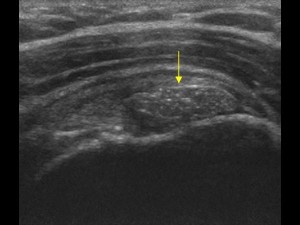

• La phase formative . Le dépôt mesure souvent moins de 1 cm. Cette phase est de durée indeterminée, et peut être associée à des douleurs. En effet, en présence d’une volumineuse calcification , cette dernière peut déformer le tendon en l’épaississant et en le « durcissant ». De cette modification de la structure tendineuse peut résulter en un conflit (une sorte de friction douloureuse) entre le tendon et l’acromion (l’os qui constitue l’épaulette). A cette phase, la calcification peut aussi être responsable d’un processus inflammatoire autour de cette dernière qui fragilise les fibres tendineuses. A ce stade la calcification a une consistance comparable à de la pate de dentifrice ou du mastic . On l’a dit pâteuse ou crayeuse (comme de la poudre agglomérée) (Fig 1). Elle peut être aussi plus dure et de type « pierreuse »(Fig 2).

(Fig2) . Calcification « dure » car peu absorbante à l’échographie.